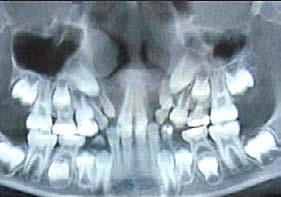

Realizar análisis en estudios de gabinete como:

a) Análisis de modelos de estudio propios de la etapa de dentición mixta, entre los que podemos mencionar:

• Análisis de dentición mixta de Moyers.

• Análisis de Howe, Sabin Sabara, entre otros.34

b) Análisis radiográficos, periapicales, ortopantomográficos, oclusales, lateral de cráneo, anteroposterior de cráneo.

c) Estudio y análisis tomográfico en tercera dimensión del cráneo a nivel maxilar y mandibular (Figura 24).

d) Fotografías intra y extraorales.

de las aparatologías adecuadas para preservar o en su caso, recuperar el espacio, considerando la edad del paciente y la complejidad del caso a tratar37,38 (Figura 25).

24.

Figura

1. La existencia y presencia de todos los elementos anatómicos craneodentofaciales (Figura 26).

3. Los desplazamientos óseos, como consecuencia de su crecimiento endocondral o intramembranoso en las diferentes zonas o áreas de remodelación, aposición y reabsorción (Figura 27).

5. La reabsorción en tiempo y forma de los caninos deciduos.

Todos los cambios dimensionales de los huesos faciales y su consecuente movimiento y remodelación, están íntimamente relacionados con los estímulos fisiológicos que activan las matrices funcionales de crecimiento, por la presencia de todos los elementos anatómicos (como los caninos), de manera adecuada, en coordinación con los demás elementos que conforman el sistema estomatognático y el sistema respiratorio35,36 (Figura 28).

Otra consideración no menos importante y con una influencia directa en los eslabones de estímulo en el crecimiento y desarrollo es la carga genética hereditaria, donde uno de los factores que pueden generar la inclusión canina es la agenesia parcial en ambas denticiones.16

Al estar ausente algún germen dental (como los laterales superiores permanentes y/o premolares de ambas arcadas, “los de mayor incidencia”),10 se inhibe la estimulación adecuada en el desarrollo óseo de esa zona específica, ya que al no existir el germen dental, la matriz ósea inhibe su crecimiento en esas zonas en específico11 (Figura 29).

maxilomandibulares, 17 las cuales propician alteraciones en el proceso del intercambio dentario; en la que una reducción de los espacios necesarios para el acomodo de los caninos y de otros órganos dentales en las arcadas, retrasa e impide que el impulso natural propio de la formación radicular como empuje fisiológico, impidiendo el desplazamiento y la erupción del canino en tiempo y una posición ideal dentro del arco dental (Figura 30).

Sumado a lo anterior, la retención generada dentro del macizo óseo basal altera su posición en angulación y dirección correcta de erupción. Situación que en ocasiones daña las raíces de los dientes adyacentes al canino y que finalmente podrá quedar incluido, en el peor de los casos, cuando no encuentra una salida de emergencia hacia el paladar o el vestíbulo12 (Figura 31).

Caries y pérdida dental

La formación de caries en la dentición decidua y la consecuente pérdida prematura de órganos dentales deciduos, en algunas ocasiones, son

consideraciones a tomar muy en cuenta como factor etiológico en la inclusión del canino (Figura 32).

Por un lado, la presencia de caries interproximales en dientes deciduos, ya sea de manera independiente o como consecuencia de caries rampantes en uno o varios dientes, propicia la disminución de la longitud y/o perímetro del arco dental, donde ya no habrá, en consecuencia, el espacio necesario para el acomodo definitivo de los caninos y premolares permanentes.14

Por otro lado, al haber una pérdida prematura de un diente deciduo, además de generar una disminución de la longitud del arco dental, la biomecánica fisiológica propia de nuestro organismo, tiende a cerrar los espacios o brechas generadas por la pérdida de algún órgano dental, mesializando los dientes distales al diente faltante y generando extrusión del antagonista inmediato (Figura 33).